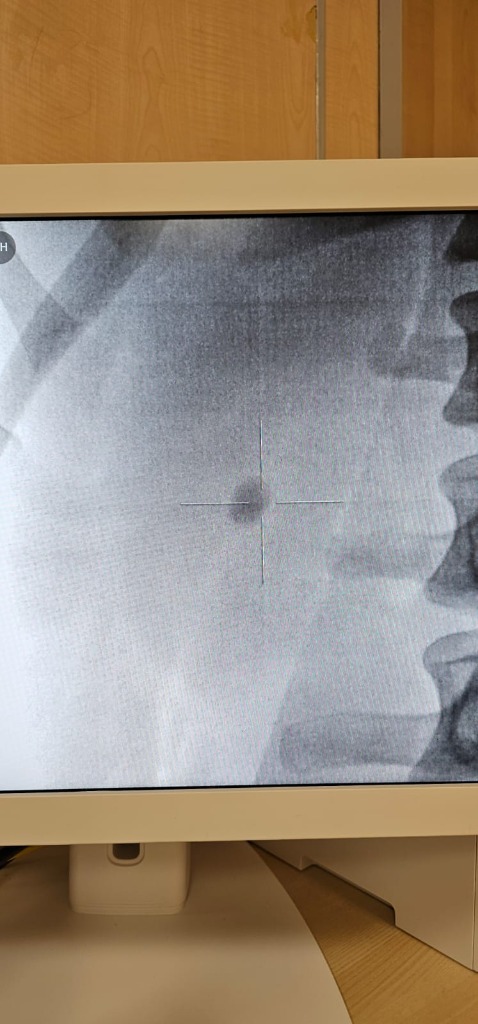

Before ESWL X-ray

Before